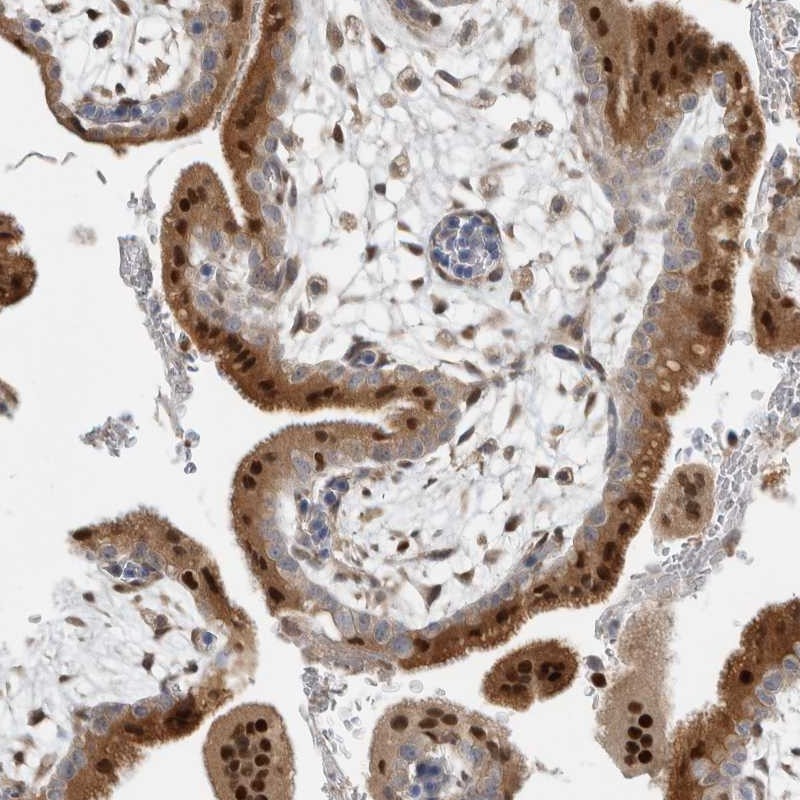

Immunohistochemical staining of human placenta shows distinct nuclear and cytoplasmic positivity in syncytiotrophoblasts.